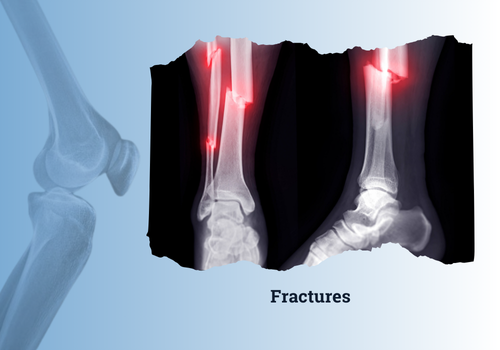

A fracture is a break or crack in a bone caused by excessive force, trauma, or underlying medical conditions. Fractures can range from simple cracks to severe breaks where the bone pierces the skin (open fractures). Proper diagnosis and treatment are essential to ensure proper healing, restore mobility, and prevent complications.